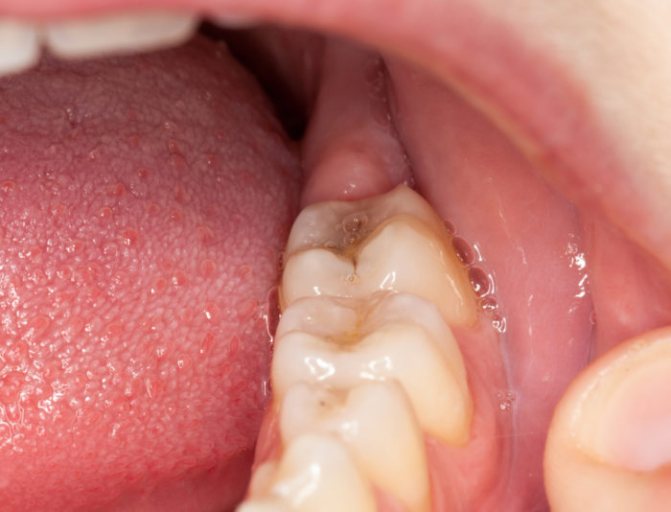

Флюс представляет собой воспалительный процесс гнойного характера, локализующийся в поддесневой и поднакостичной челюстных зонах. Когда стоматолог диагностирует такой диагноз, то у пациента возникает вопрос, а нужно ли удалять зуб. Все зависит от характера проблемы.

Флюс – это устаревшее название периостита, представляющего собой воспаление надкостницы, которая является соединительнотканной пленкой, покрывающей челюстную кость. Она играет ключевую кровоснабжающую и костеобразующую роль, поэтому ее заболевание негативно сказывается на здоровье и может привести к тяжелым последствиям вроде сепсиса. Причиной периостита в 90% случаев являются пульпит или периодонтит — воспаление внутренних или окружающих зуб тканей.

Развитию патологии сопутствует локальный отек десны, который со временем увеличивается, причиняя пациенту болевые ощущения. Спустя сутки или двое формируется абсцесс: гнойное воспаление тканей с их последующим расплавлением, которое в данном случае приводит к опуханию всей щеки и губ.